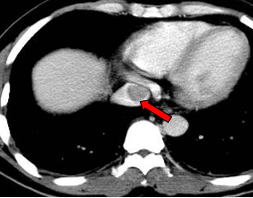

现病史:2011年01月4日于当地医院行PET/CT: 1. 肝左外叶肝癌并肝门区淋巴结转移,2. 下腔静脉及右心房结癌栓,考虑为”原发性肝癌“。

影像学检查:

2011-01-06我院上腹部CT:

肝左叶巨块型肝癌(13.8cm×9.1cm),伴肝右后叶子灶,门静脉左支、肝左静脉及下腔静脉内癌栓。